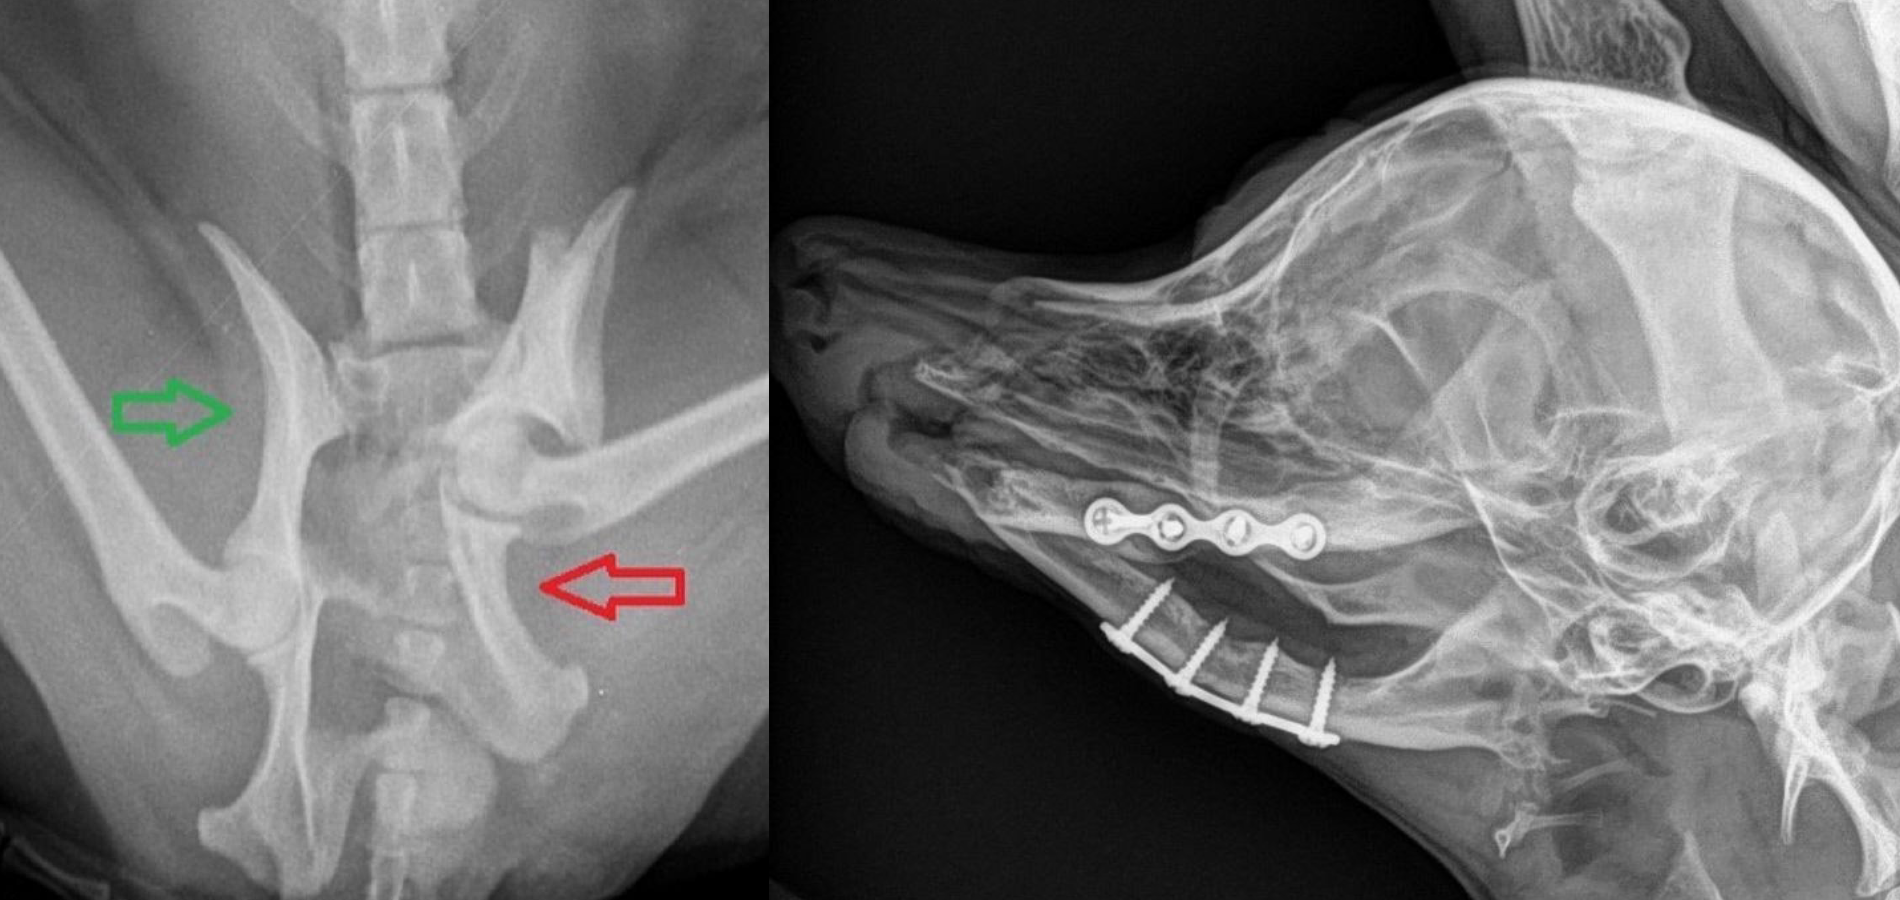

(Переломы таза и челюсти у собак после автотравмы)

У собак это чаще всего происходит из-за ДТП или драки с другими животными. Лучше всего приучить собаку к выгулу в ошейнике или шлейке, так же приучить к ношению намордника, контролировать контакт с другими животными. Если выгул производиться на частной территории или специально ограждённых местах, лучше всего обеспечить безопасную среду для выгула своего питомца.